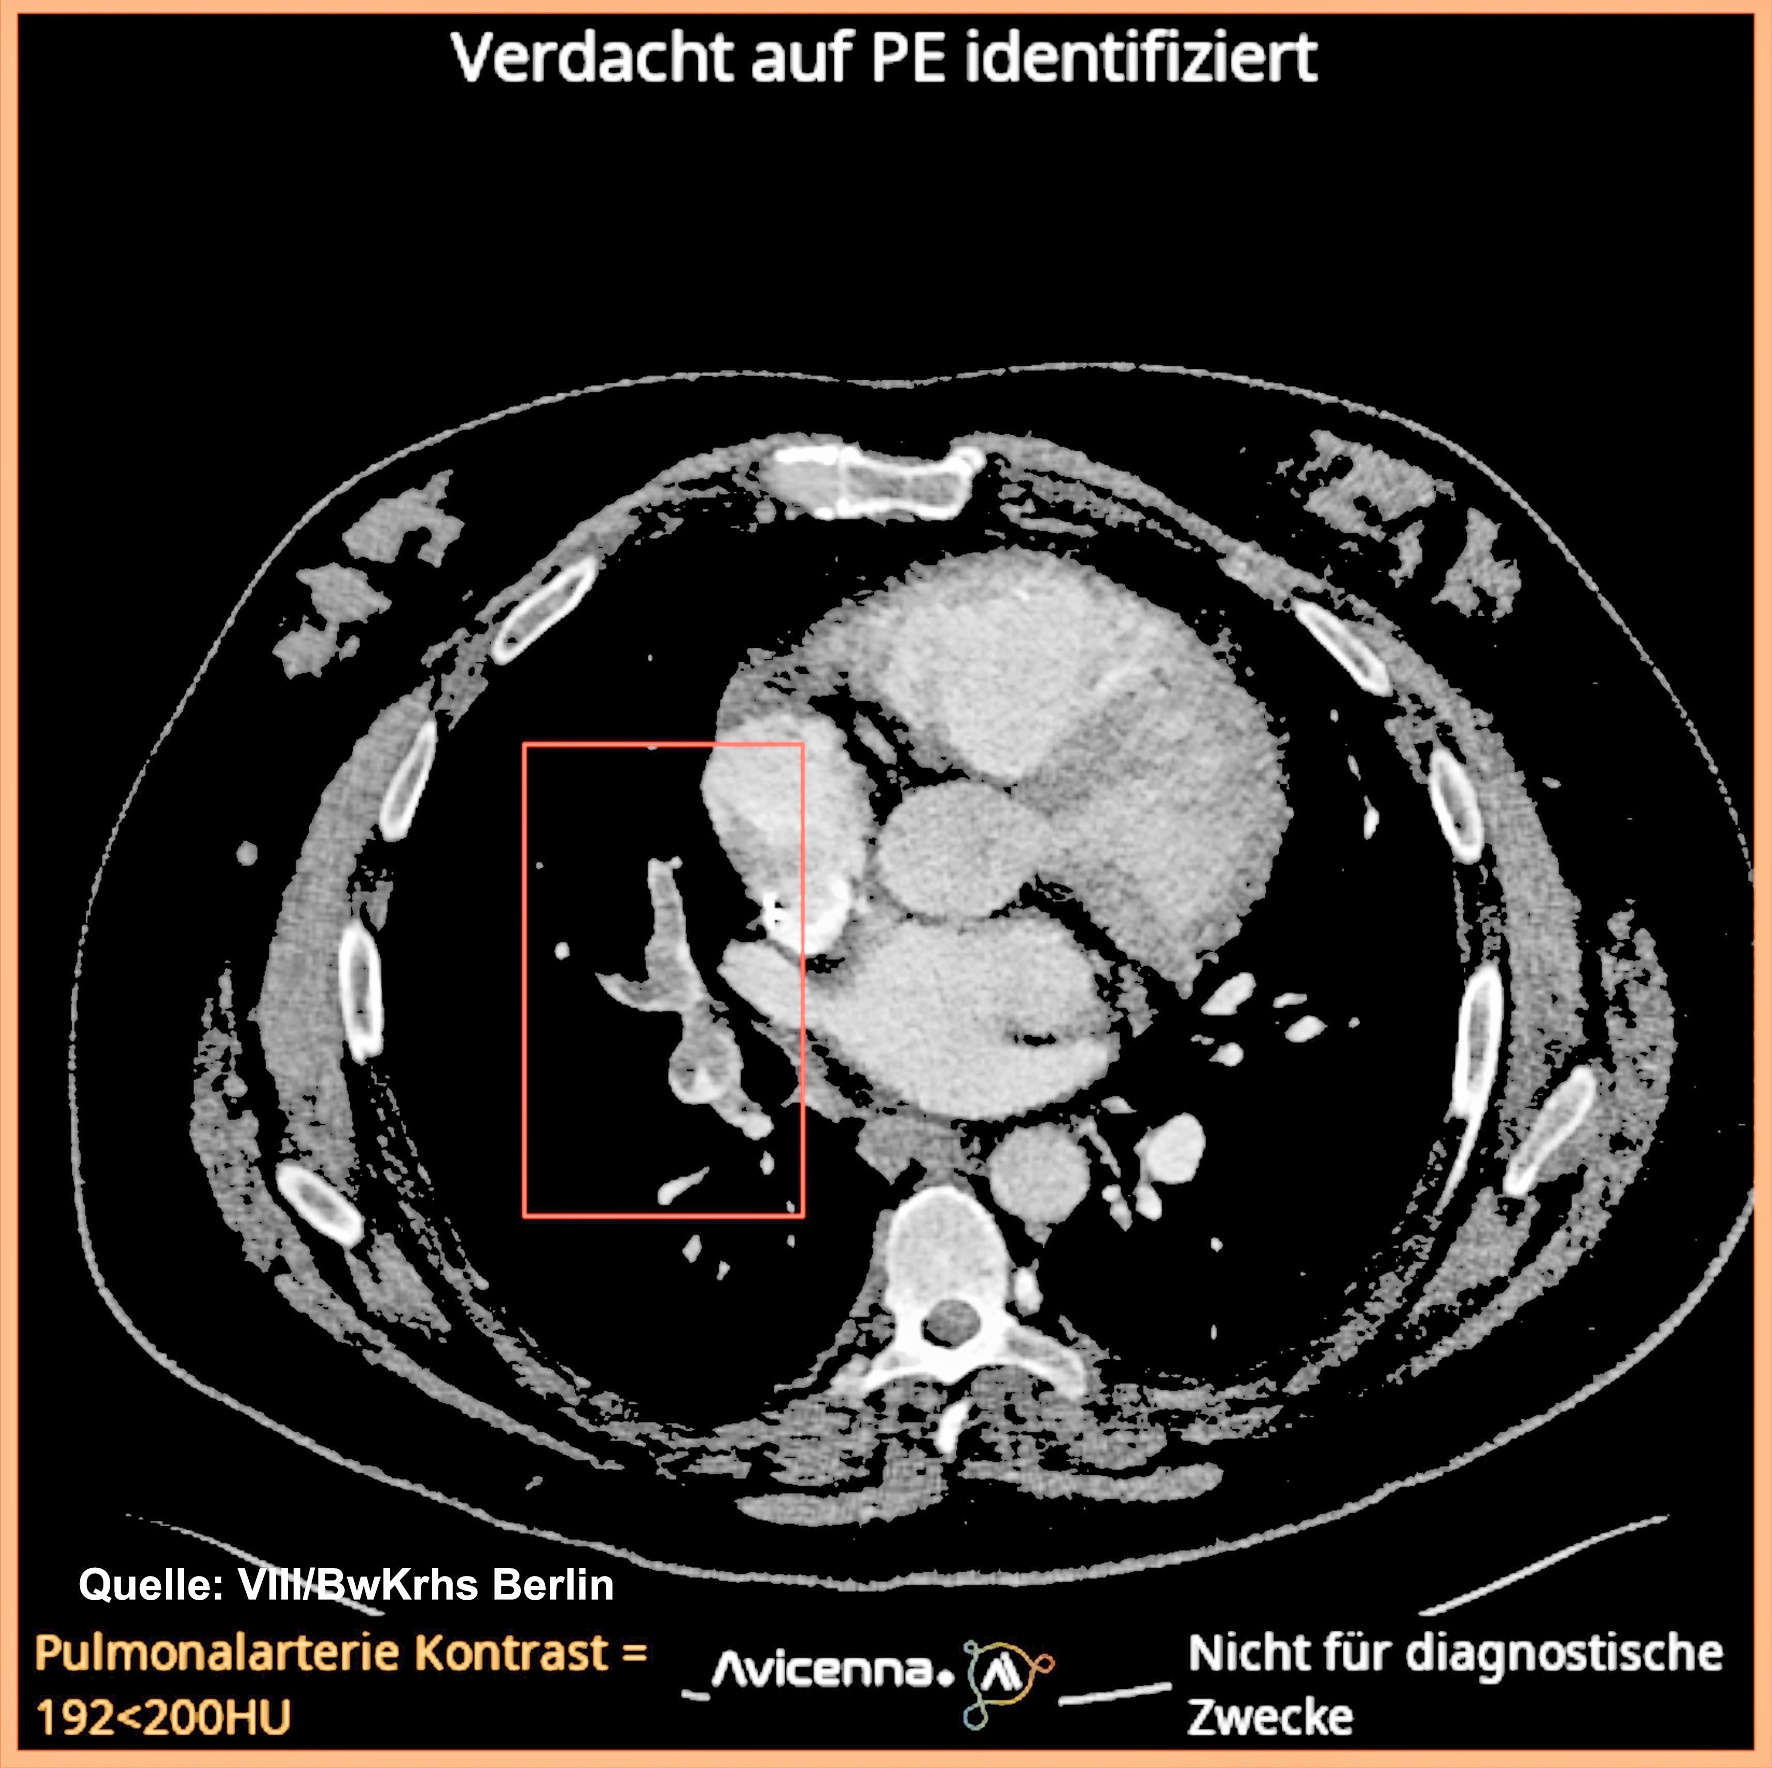

Das Polytrauma zählt im Rahmen kriegerischer Auseinandersetzungen, insbesondere in Szenarien der Landes- und Bündnisverteidigung, zu den häufigsten und komplexesten Verletzungsmustern. Für eine zielgerichtete Triage und…